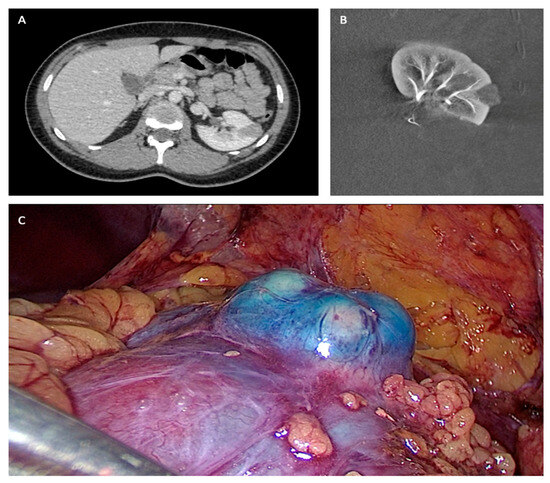

*Long-Term Oncological and Functional Outcomes after Laparoscopic *